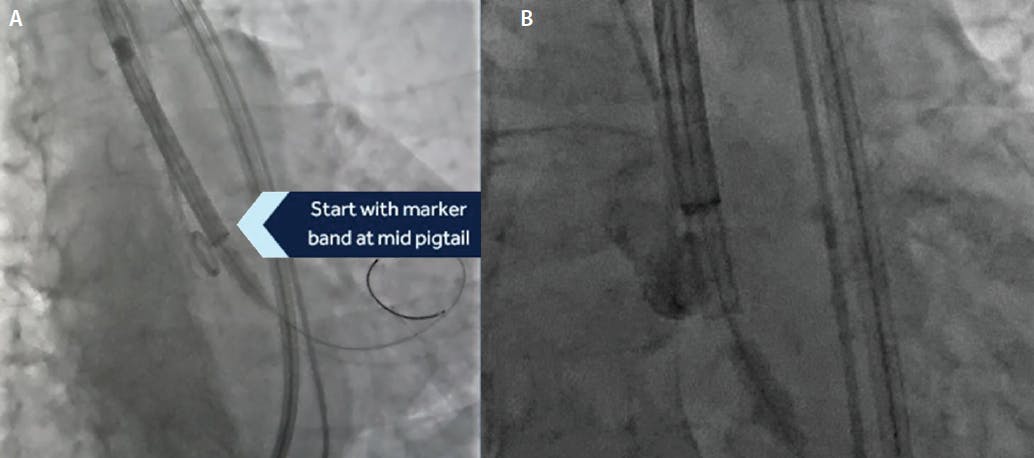

In addition to the cusp overlap view, several procedural steps have been embedded in this technique to further reduce interaction with the conduction system during TAVR deployment. We now focus on more of a “top-down” deployment of the THV, starting with the catheter marker band positioned at the midportion of the pigtail in the NCC (Figure 3). With retraction of the nitinol capsule, the inflow of the prosthesis advances across the annulus and is positioned at 3 mm below the annulus. This maneuver avoids traumatic advancement of the bioprosthesis into the ventricle with inflow flaring deeper within the left ventricle, resulting in subsequent maneuvers to move it more aortic and interacting with the muscular septum and conduction system. We also use a stiffer, double-curved, Lunderquist wire (Cook Medical) in most cases to maintain a wire position in the non-right commissure and begin the prosthesis deployment along the posterior aspect of the annular plane. The stiffer wire may result in more symmetrical deployment and is especially valuable when deploying larger-sized THVs. Using the cusp overlap view to maintain a reference to the native annular plane, the marker band on the THV delivery catheter does tend to lose parallax when approaching the valve plane. The loss of parallax of the marker band is the result of the delivery catheter following the stiff left ventricular wire that is generally positioned in the NCC/RCC commissure. This approach may lead to more confidence in the initial positioning of the THV in relation to the insertion of the NCC and a better assessment at the point of no-recapture. We also favor sufficient pacing during the deployment to minimize cardiac output and the occurrence of premature ventricular contraction burden, allowing for a stable bioprosthesis deployment. Finally, once we are at 80% deployment, we rotate the gantry to an LAO projection to visualize the LCC and ensure that the inflow is not supra-annular. We aim for an implantation depth of 3 mm, and no deeper than 5 mm, below the NCC to reduce our risk of conduction disturbance. We occasionally aim for shallower deployment in patients at high risk for conduction system abnormality but recommend recapture for bioprosthesis positions < 1 or > 5 mm within the ventricle. Once final positioning is confirmed, we retract the left ventricular wire, centralize the nose cone, and slowly release the delivery catheter from the bioprosthesis by the release of the frame paddles. We are cautious to avoid interaction of the delivery catheter and the bioprosthesis as the delivery catheter is retracted into the aorta.

Figure 3. Location of the marker band at initial deployment. The marker band is placed at the mid position of the pigtail catheter that is positioned at the lowest portion of the noncoronary sinus (A). With retraction of the nitinol capsule, the inflow of the Evolut bioprosthesis advances to a 3-mm position below the annulus (B).